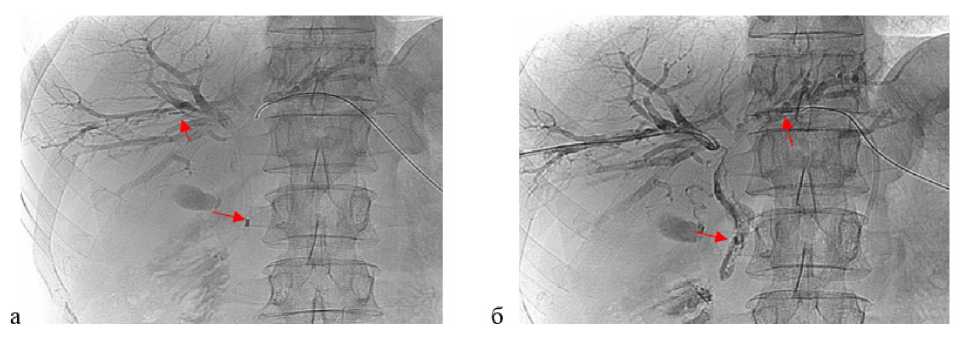

Всем пациентам выполнена верификация онкологического процесса с применением оригинальной запатентованной методики видеоассистированной внутрипротоковой щипковой биопсии под рентгеноскопическим контролем [23]. Сущность метода заключается в чрескожной антеградной холангиоскопии как метода определения истинного расположения опухоли. На проводнике производили удаление НВЧЧХД, далее по проводнику под рентгеноскопическим контролем за дефект контрастирования заводили интродьюсер 10 F, проводник удаляли. Через интродьюсер за зону опухолевой окклюзии вводили ультратонкий эндоскоп CMOS – серия 11102 СМ – Karl Storz (Германия; 2,9 мм = 8,7 F). После выявления истинного расположения опухоли интродьюсер подводили к концевой части эндоскопа. После чего эндоскоп удаляли, фиксируя положение интродьюсера. Далее через интродьюсер заводили эндоскопические щипцы для биопсии с шагом 1,5–2 мм и выполняли биопсию под рентгеноскопическим контролем (рис. 1). Во всех случаях объем полученного биоматериала был достаточным для гистологического и иммуногистохимического исследования.

Рис. 1. Видеоассистированная внутрипротоковая щипковая биопсия под рентгеноскопическим контролем. а — рентгенограмма: ультратонкий эндоскоп установлен в месте выявленной опухоли на уровне конфлюенса общего печеночного протока; б — рентгенограмма: прицельная щипковая внутрипротоковая биопсия опухоли общего печеночного протока с использованием биопсийных щипцов